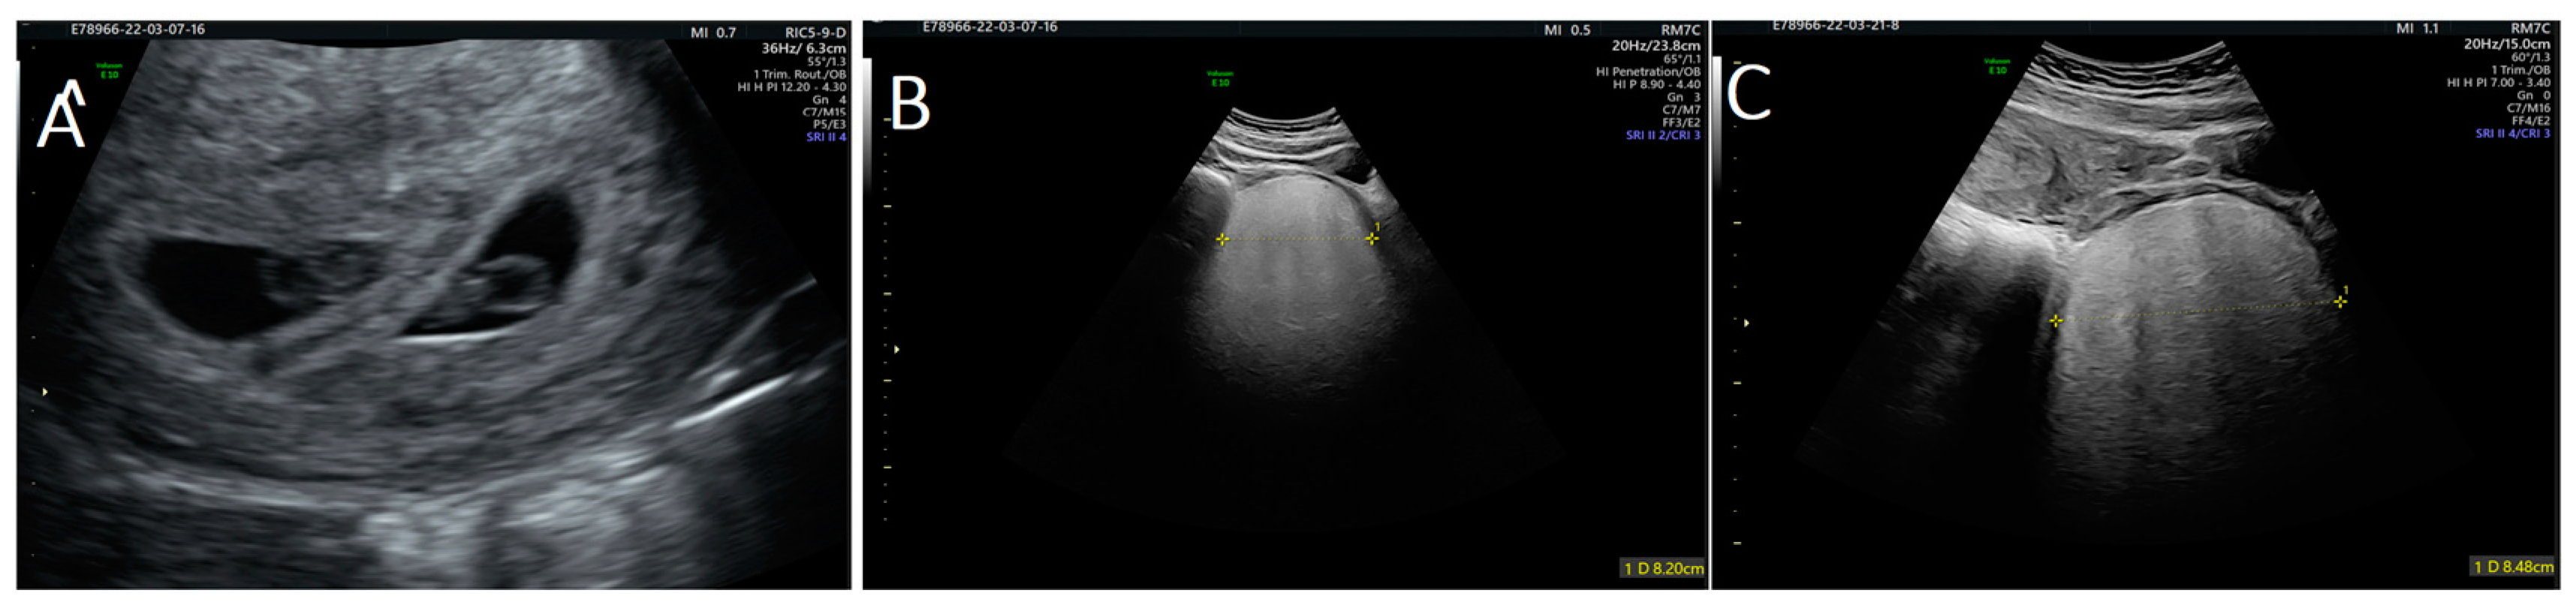

| 1 | Current case | 30 | Hypervascularized and inhomogeneous pelvic formation at ultrasound check | 10 cm in maximum diameter at 10 weeks of twin gestation | Left perineal area | Surgical excision at 13 weeks and 6 days; after, cesarean section at term |